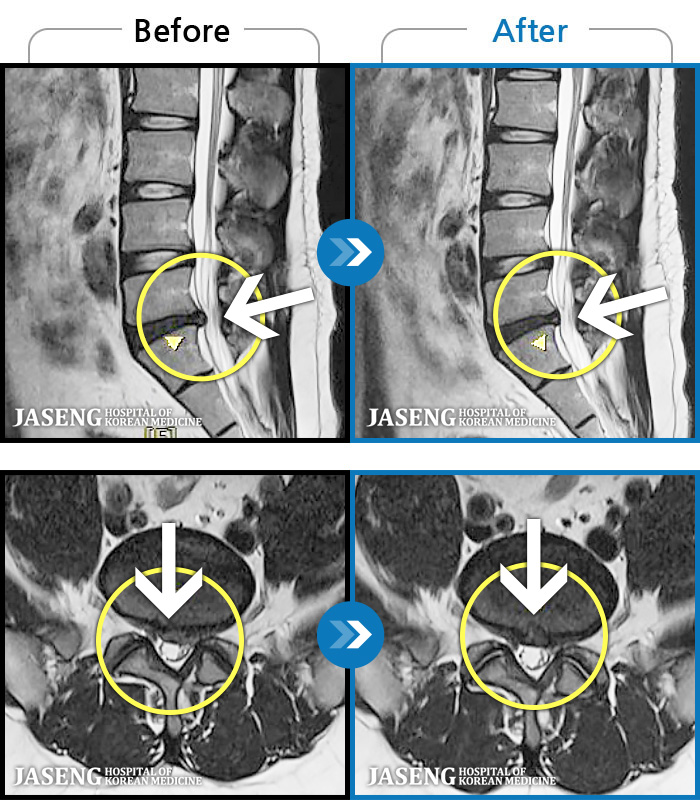

- MRI ġ

MRI ġ

97 MRI ũ ʸ Ȯϼ.

[_㸮ũ] 㸮 , ٸ ȭǾ ϼ̽ϴ.